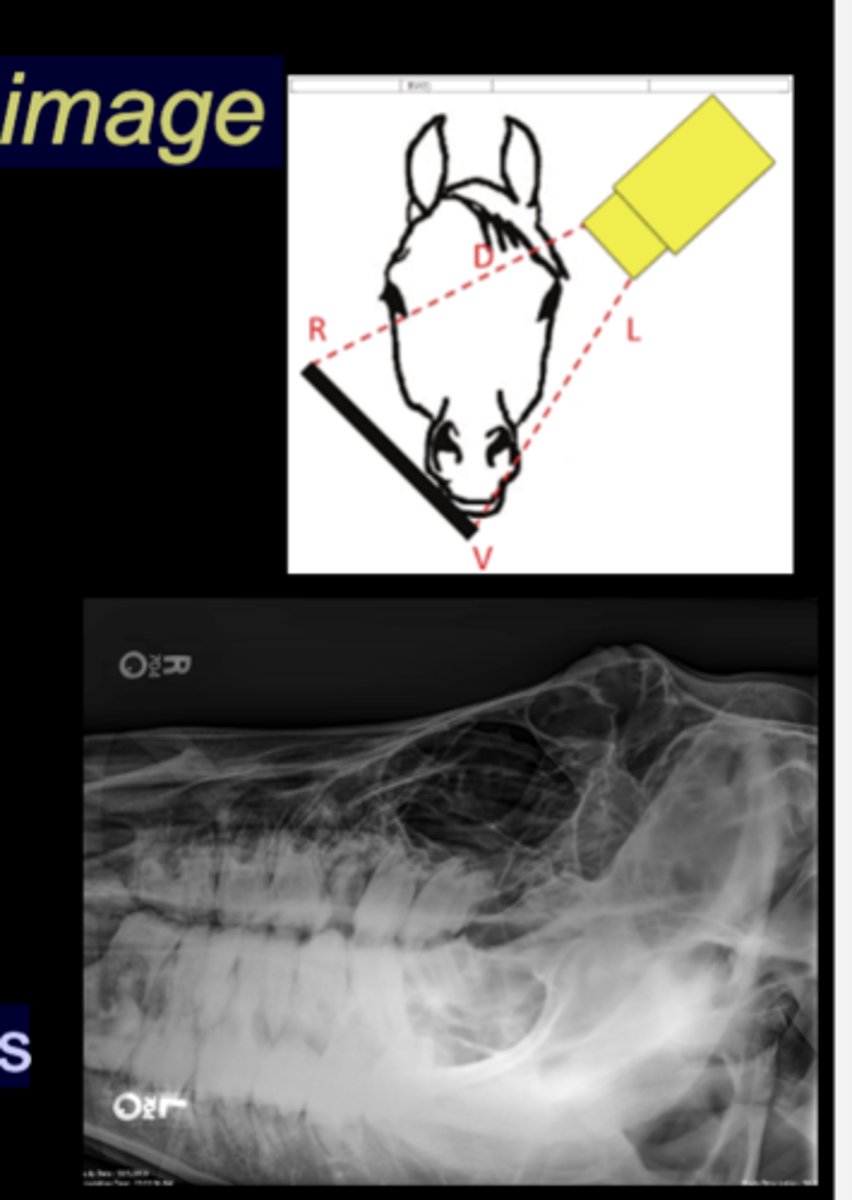

LG Animal Skull - DV Oblique image

• Tube on one side, plate on the other

• Tube angled in DV plane, plate held perpendicular

• Markers indicate anatomy that is closest

• Maxillary or mandibular structures

Llama Spine Lateral